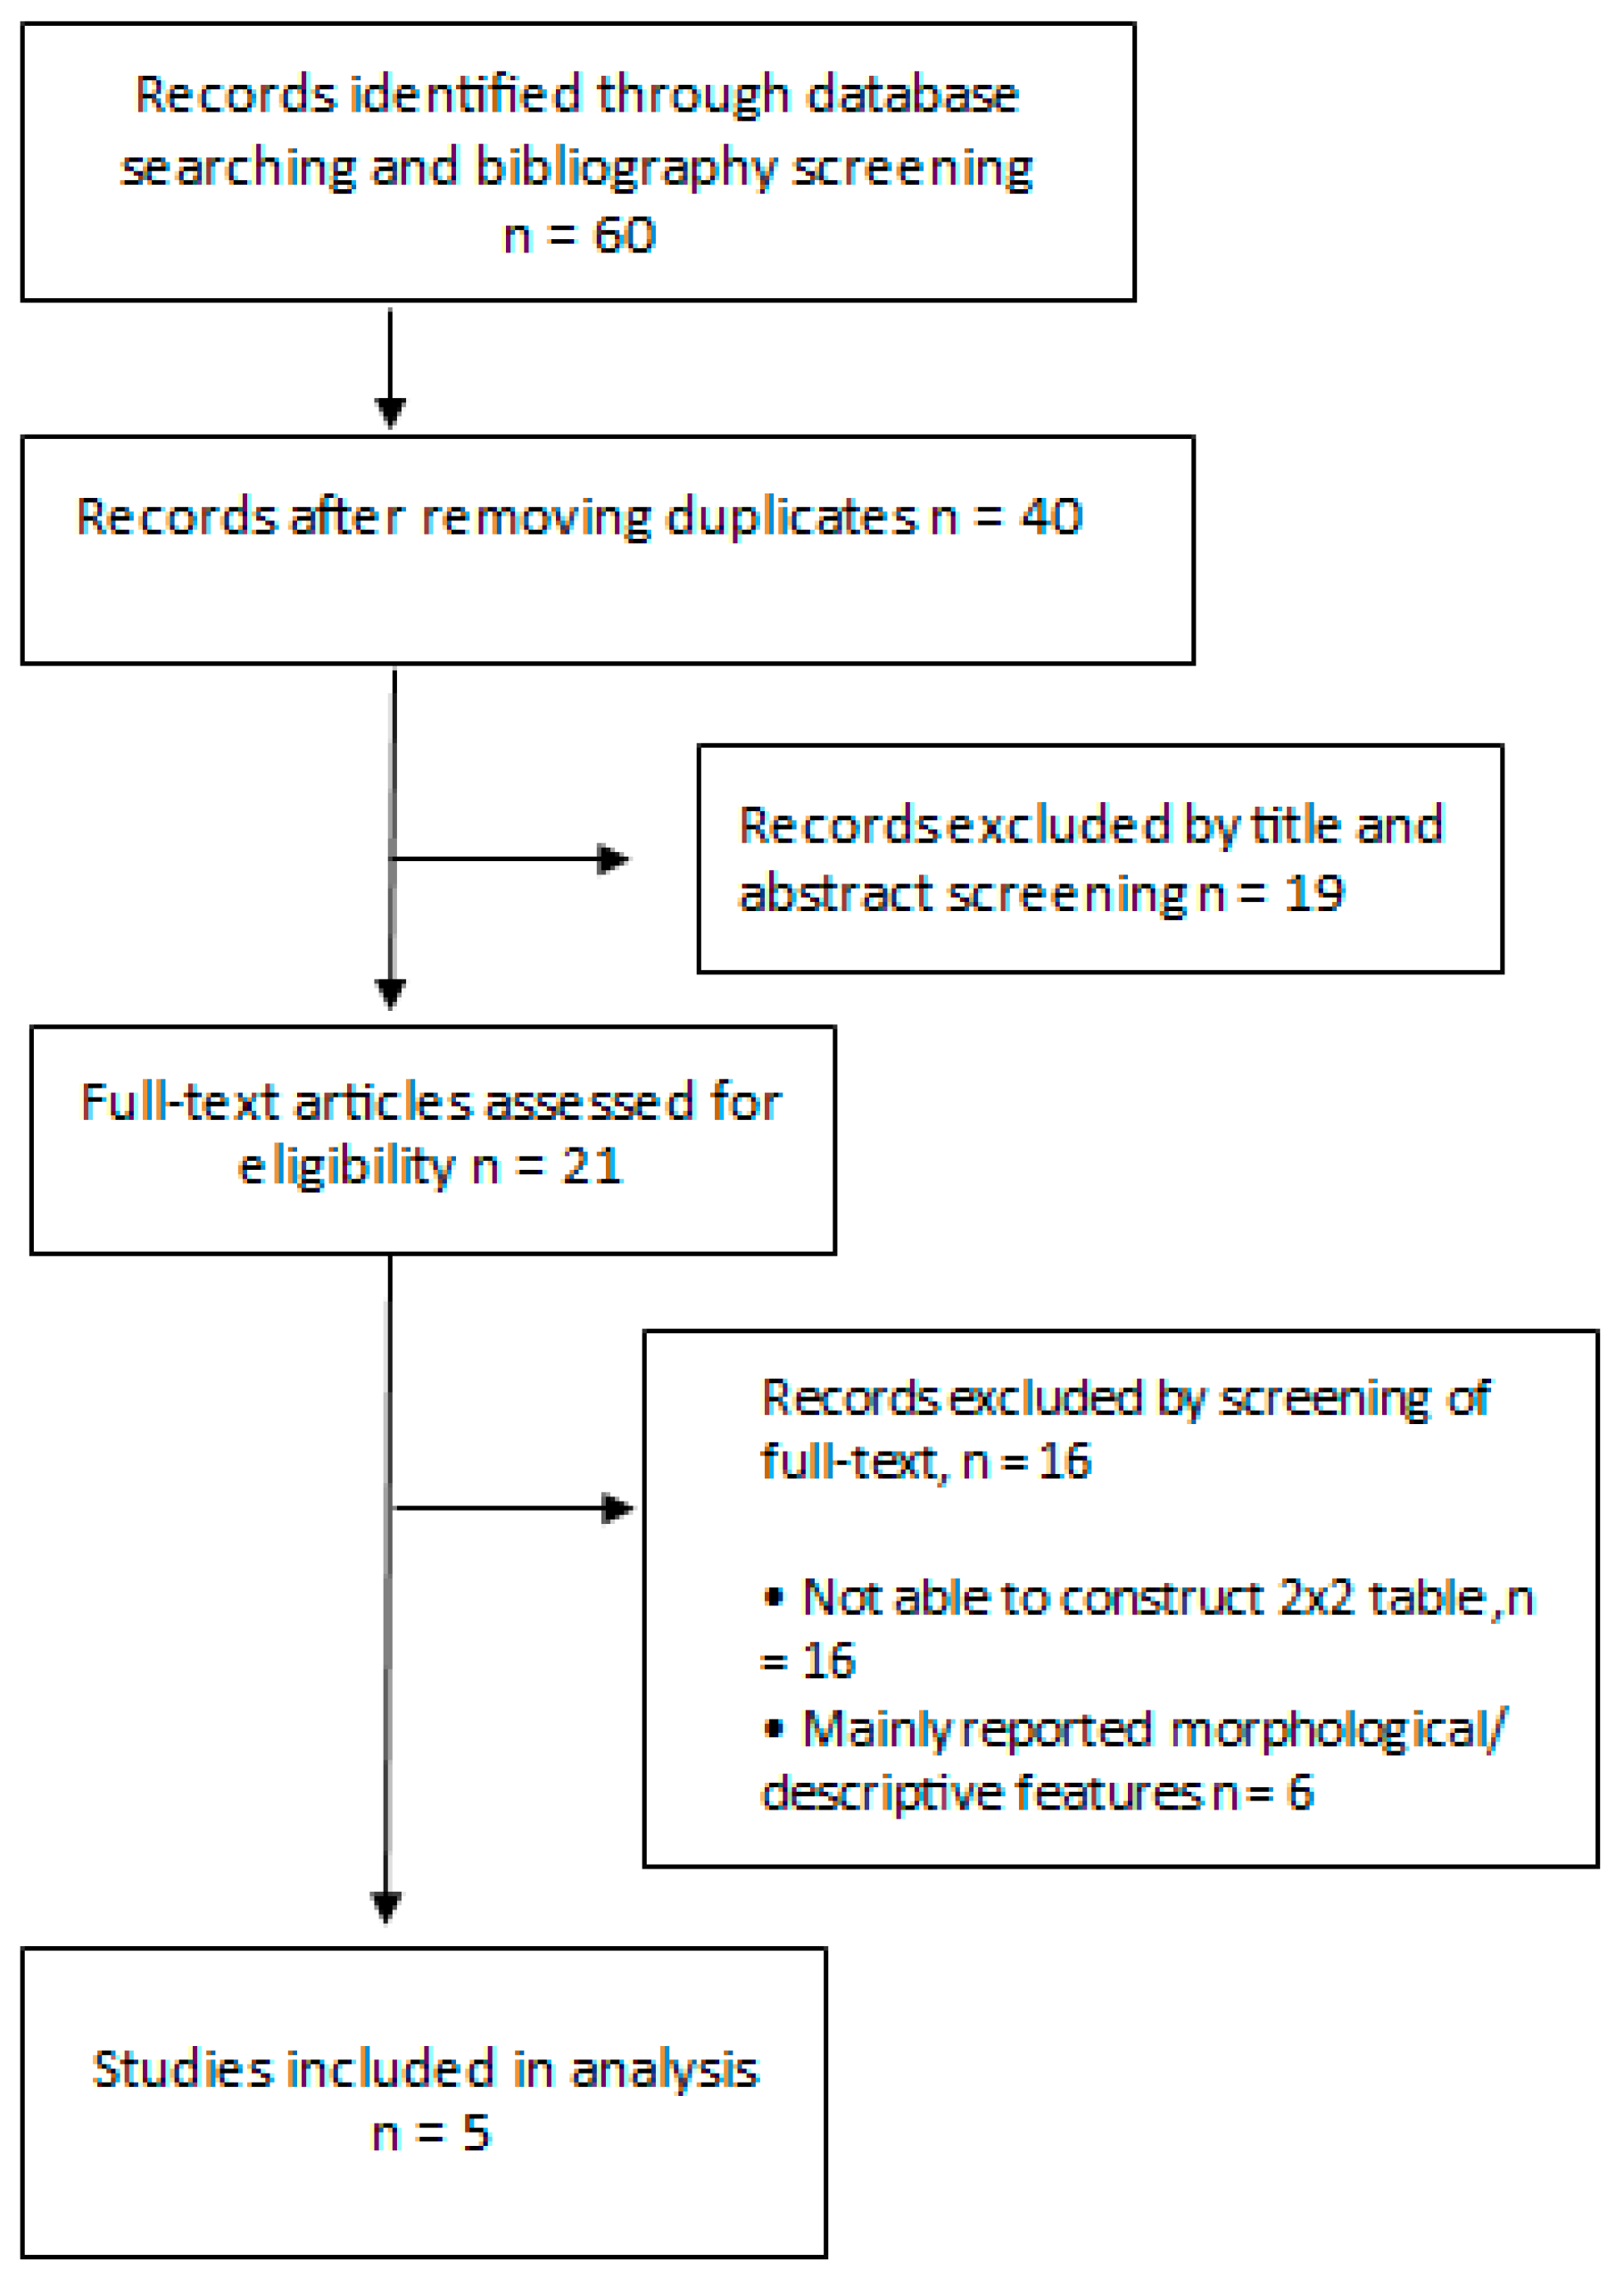

2. Materials and Methods

2.1. Literature Search

2.2. Data Selection and Extraction

3. Results

3.1. Description of Studies Included